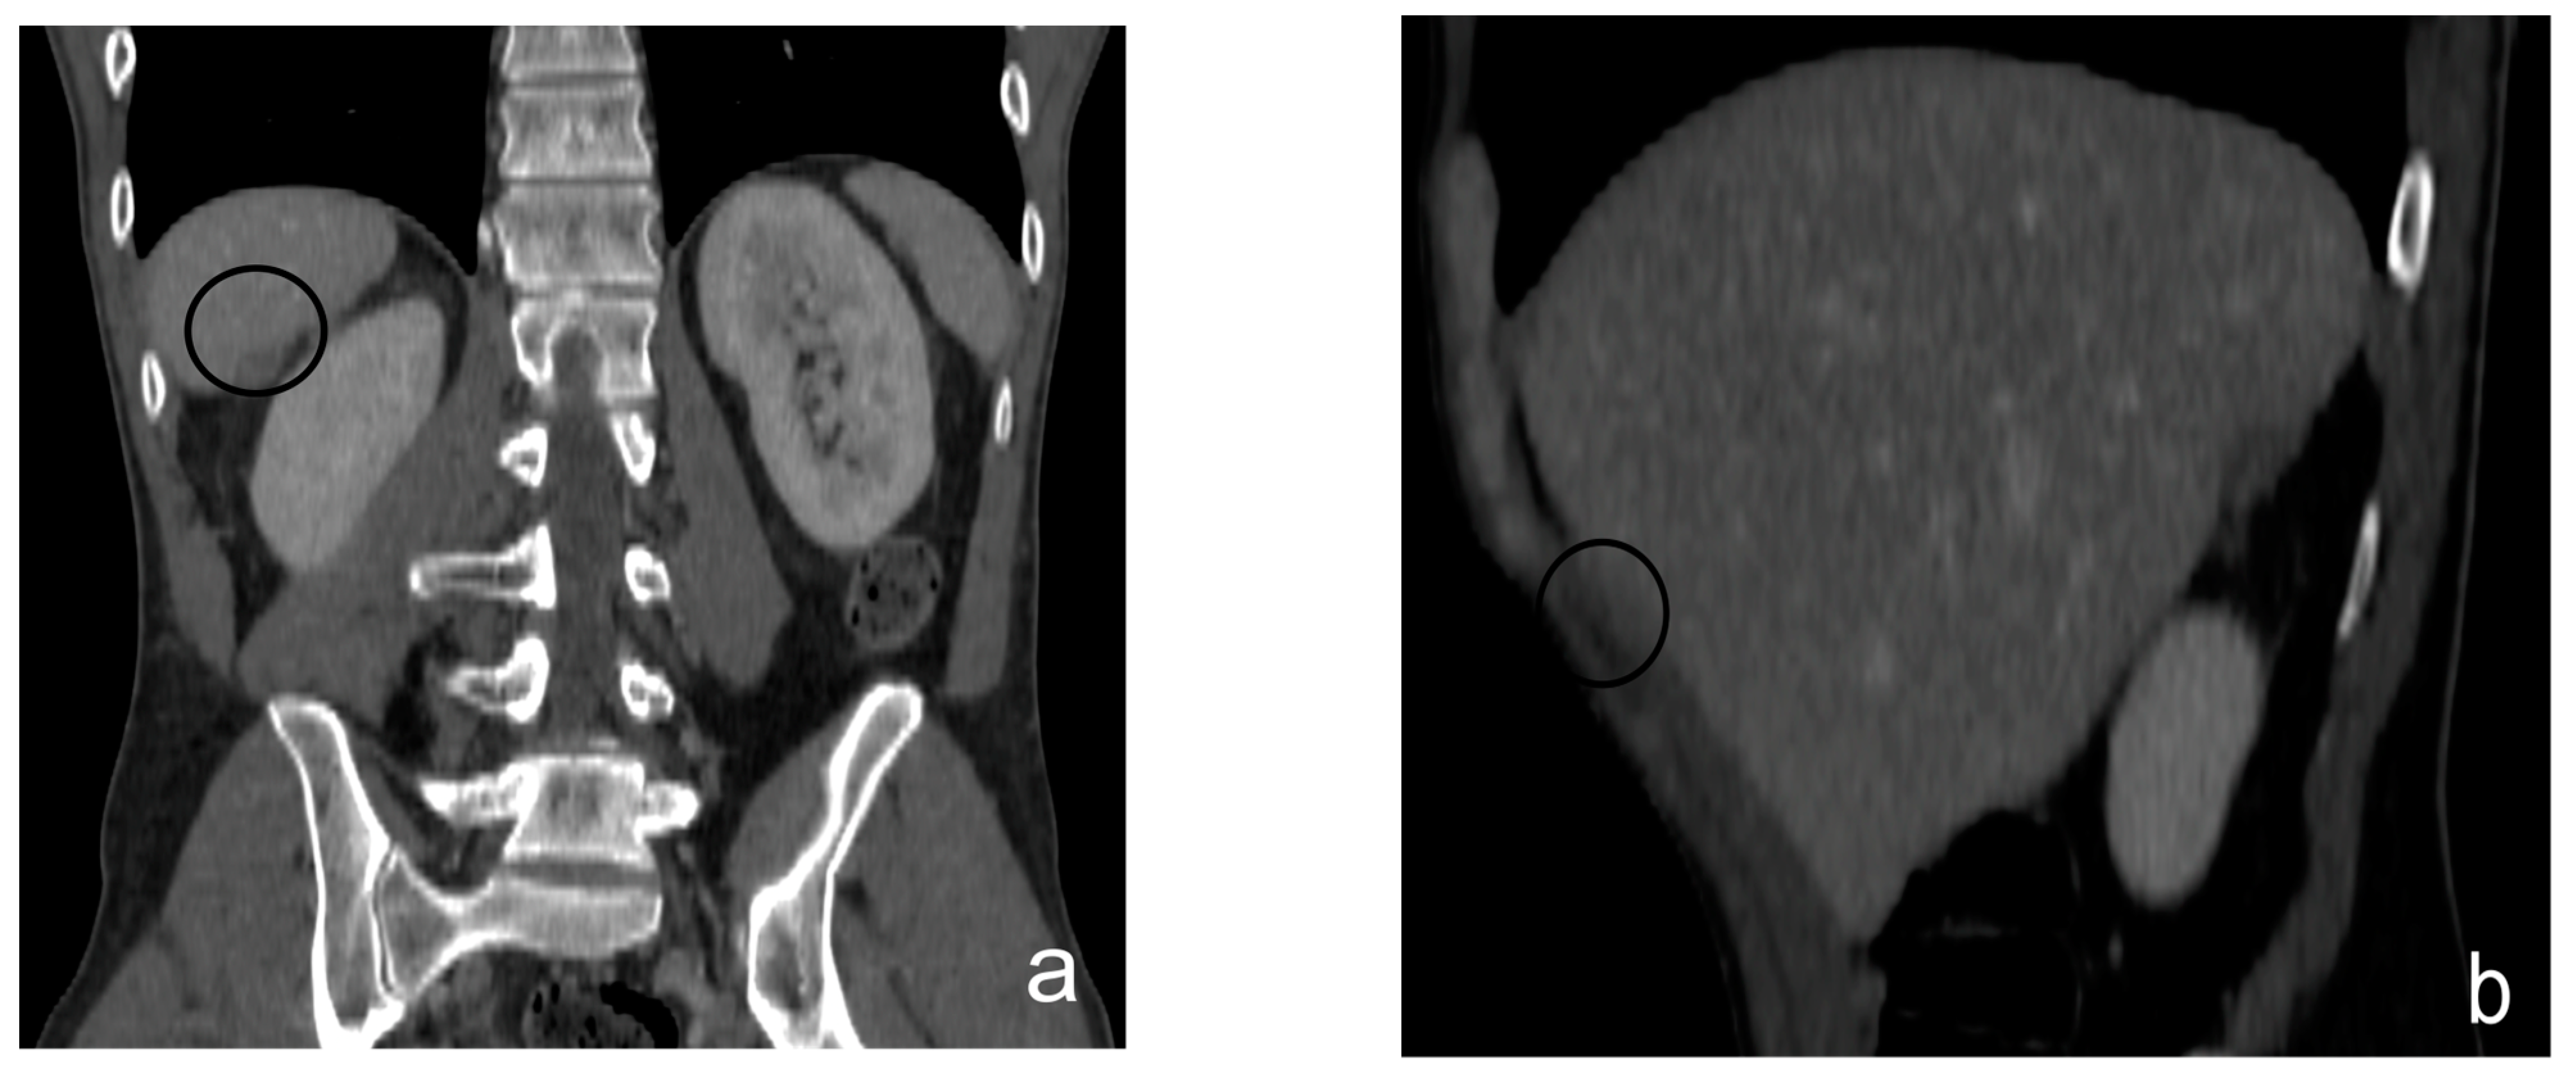

- Nodular pattern: characterized by the presence of nodular implants >5 mm in diameter (Figure 8).